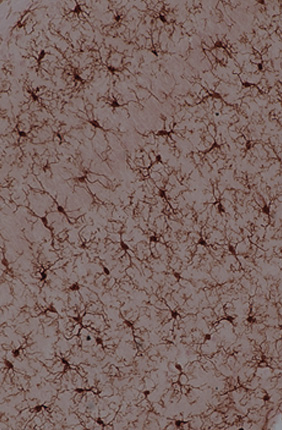

Mitochondrial protein plays key role in glioblastoma and therapeutic resistance